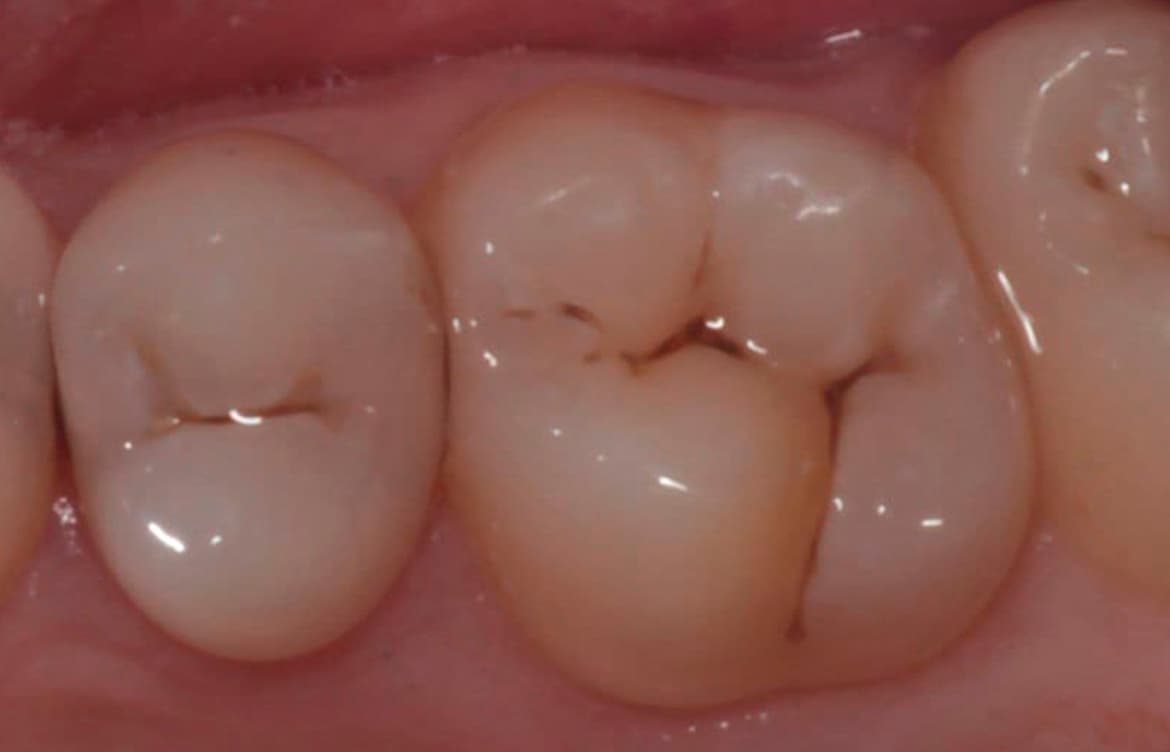

Наши работы